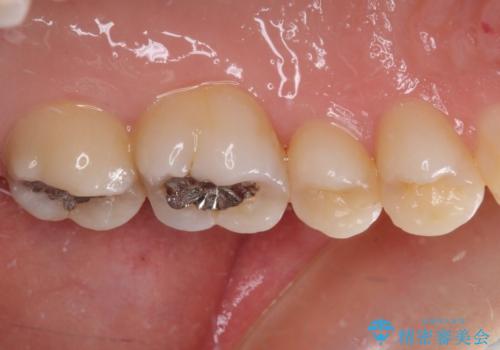

- 近医にてむし歯治療を行った後に痛みが出たとのことで来院された患者様です。

左下奥歯は術後から咬合時の痛みが発現し、来院時には脈を打つような痛みが認められました。

診察の結果、神経を取り除く必要があると判断されたため根管治療を行いました。

その後、左上の奥歯にも咬合時の痛みが認められ、レントゲン写真より歯内の神経が失活していることが分かりました。

2歯ともに根管治療を行い、その後はオールセラミッククラウンにて補綴治療を行うこととしました。